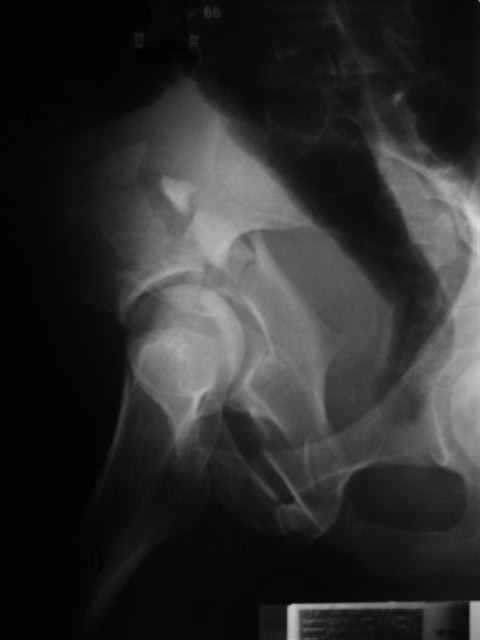

Уважаемые коллеги,43 летний мужчина, попав в автоаварию 13.10.2004, получил оскольчатый перелом обеих колонн левой вертлужной впадины.

На рентгенограммах - высокий двухколонный перелом вертлужной впадины с нарушением конгруэнтности, имеется обратная клиновидность суставной щели.

Спасибо за комментарии и рекомендации. Откровенно говоря, больного я прооперировал на прошлой неделе, через 5 дней после аварии и проблем с ним пока никаких нет, на удивление при достаточно обширной диссекции (илиофеморальный доступ) болей практически нет, так что больной самостоятельно садится в кровати, выполняет активные движения в оперированном суставе, сгибая до 60 градусов пока, далее с ассистенцией.

Причиной обращения к сообществу были возникшие непосредственно после операции сомнения и разочарования полученным качеством репозиции: а надо ли было трогать перелом вообще, репозиция передней колонны технически была очень сложна для меня, хотя реконструкции была в той же последовательности, что Д-р А.В.Рунков рекомендовал, в какой-то момент безуспешных манипуляций стал думать о *вторичной конгруэнтности*, которую не так давно обсуждали на

форуме и скелетном вытяжении. С репозицией и фиксацией задней колонны и отдельно задне-верхней стенки впадины проблем не возникло. Послеоп. Рг граммы в приложении. Если возникнут какие-либо дополнения или поправки - был бы признателен.